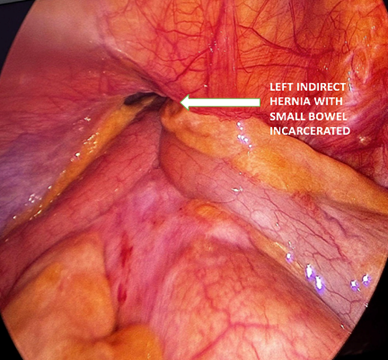

We then switched sides between the surgeon and the camera. The right hernia was a direct defect 5cm in diameter and practically over the midline on what appeared to be de suprapubic space, with heavy fibrosis on the ring and no apparent content in the sac. The peritoneal flap was done the same way, but when we progressed to dissect the sac, we noticed that the peritoneal sac covered completely an incarcerated bladder hernia, so dissection continued with extreme caution to avoid bladder injury. Approximately eighty percent of the bladder was reduced from the defect. The peritoneal flap was extended and joined with the one on the left side to obtain a complete view of the pelvis and the bladder which had no signs of injury and it started to fill with urine (Figure 3).

Figure 3 Massive bladder hernia reduced.